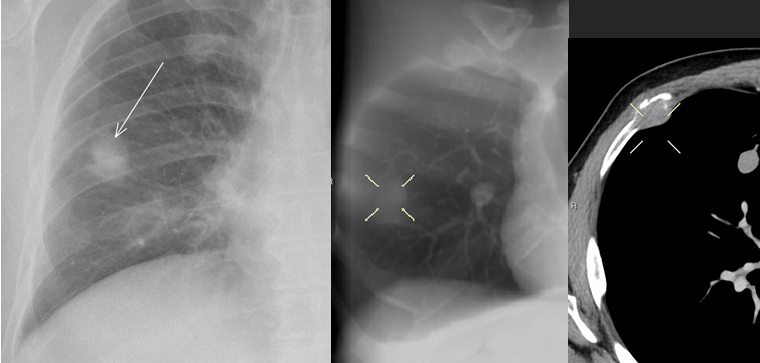

Métastase Cavitaires

- Carcinome Epidermoide ++ (ORL et Poumon)

Cas

Metastases Costales

Meta de liposarcome

Meta de liposarcome